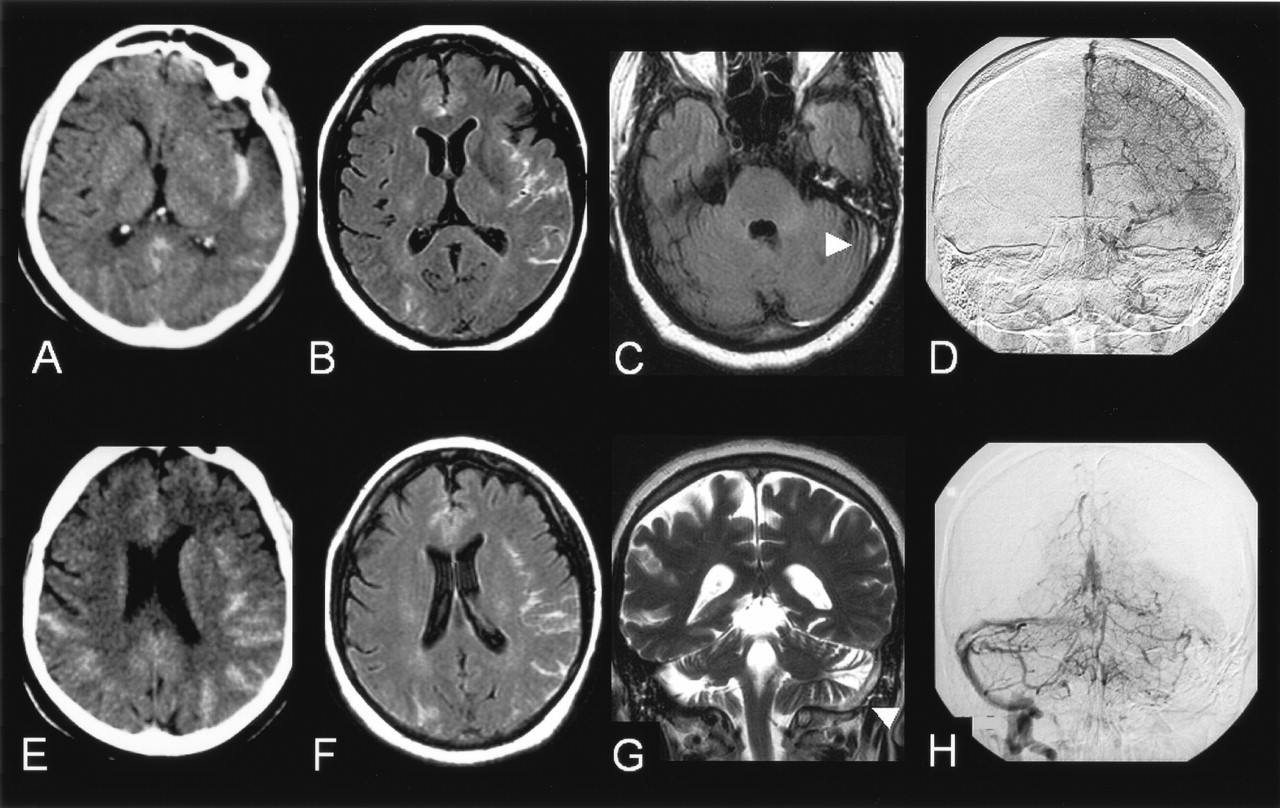

Case 2.

A, E, Plain CT scan showing a bihemispheric subarachnoid hemorrhage, predominating in the left insular sulci.

B, F, FLAIR images (9800/152/2300/1) showing hyperintensities within the subarachnoid spaces.

C, FLAIR images (9800/152/2300/1) showing absence of signal changes in the basal cisterns and revealing a hyperintensity within the left transverse sinus (arrow).

G, T2-weighted image (7000/86.3/2) in the frontal plane confirming the presence of a hypersignal within the left transverse and superior sagittal sinuses (arrows), raising the suspicion of sinus thrombosis.

D, H, Venous phase of the digitized subtracted angiogram (A–P views) of the left carotid (D) and the left vertebral (H) arteries confirming the occlusion of the left transverse and superior sagittal sinuses. The right transverse sinus is not seen medially but fills laterally from venous collaterals and drains into the right sigmoid sinus.